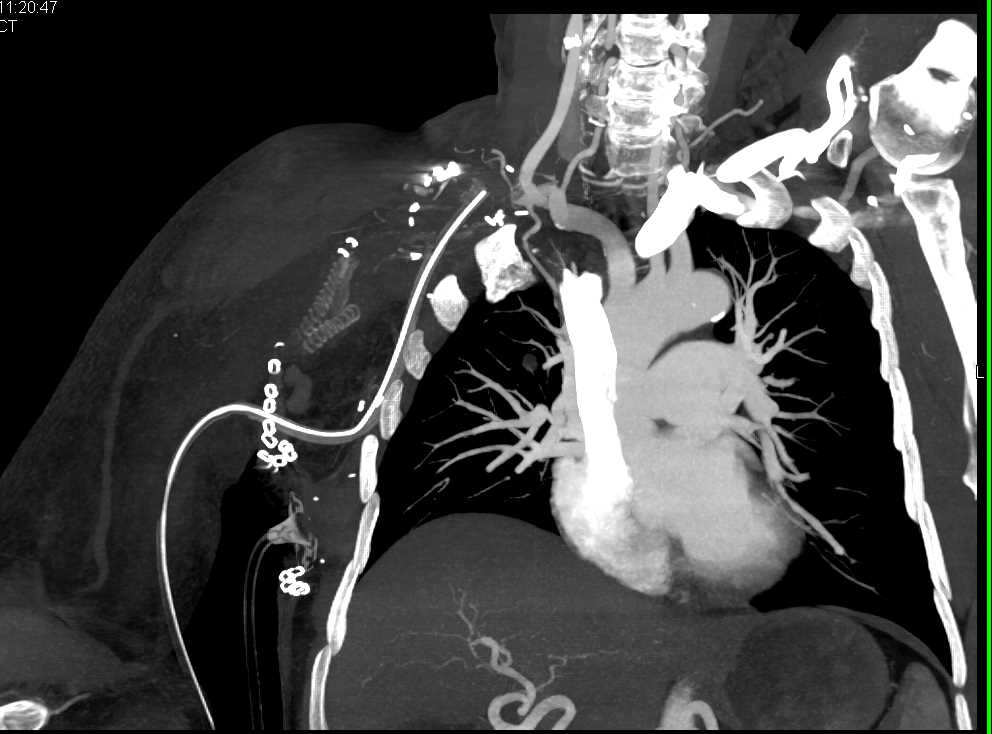

Type A Dissection with Repair